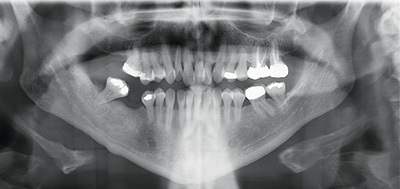

Diagnosing from “outside-in,” she showed lower 1/3 vertical facial height in slight excess, a prominent chin and mild mandibular asymmetry to the right. Unfavorable dark triangles are obvious in her smile because of periodontal recession. She shows only mild Class III occlusion, but a significant number of teeth are in full crossbite position. Notable cephalometric findings include mild mandibular prognathism, a high mandibular plane angle and lower incisors that are slightly compensated/upright as you might expect with a Class III excess mandible. Multiple areas of varying bone loss are present and the LR8 was given a poor long-term prognosis by the dentist.

Orthognathic surgery was discussed with Shelley as the most ideal plan, with a lesser risk of periodontal stress compared to the non-surgical plan, but Shelley declined that ideal option. When I had Shelley open slightly, I could see that her lower jaw dropped down and back enough to bring her into an edge-to-edge bite with the upper left central incisor. I knew that if I could disclude her properly, unravel the upper crowding and close the minimal space on the lower, her occlusion should fall very close to where we would need it. The big decision in this case was where and how to disclude her.

I felt that choosing to place the bite turbos on posterior teeth would be unfavorable for two reasons. First, posterior turbos tend to limit posterior extrusion and overall vertical opening. Posterior extrusion and vertical opening of the MPA alone favor occlusal correction of Class III to Class I and underbite correction as the lower jaw rolls slightly down and back. Second, in Shelley’s case, if the posterior teeth were intruded at all, great care would be needed at the end of treatment to make sure that these teeth completely settled into full contact to prevent a harder than ideal occlusion on the anterior teeth (the lower incisors show significant periodontal loss).

I also felt that placing the bite turbos on the incisors, perhaps in a Class III ramp bonded to all the lower incisors, would also not be as ideal in her case. While a Class III ramp is an excellent choice for mild Class III patients with an underbite, Shelley has compromised support for her lower incisors, and I would not choose to concentrate the force of her bite on those teeth.

Instead, the turbos were placed on the lower canines and first bicuspids. These teeth, and the maxillary canines that would abut them, showed relatively good periodontal support and longer roots. They could likely shoulder the concentrated masticatory load in this periodontally compromised patient for more than a few months of treatment if needed. Also the turbos were shaped into a ramp (they sloped in to the lingual) to give function to their form. As the maxillary canines (which were in crossbite) hit the ramps, there would be a labial crown-tipping effect to jump their position out of crossbite as the maxillary teeth aligned. Crossbite elastics also played an important role in this regard as well.